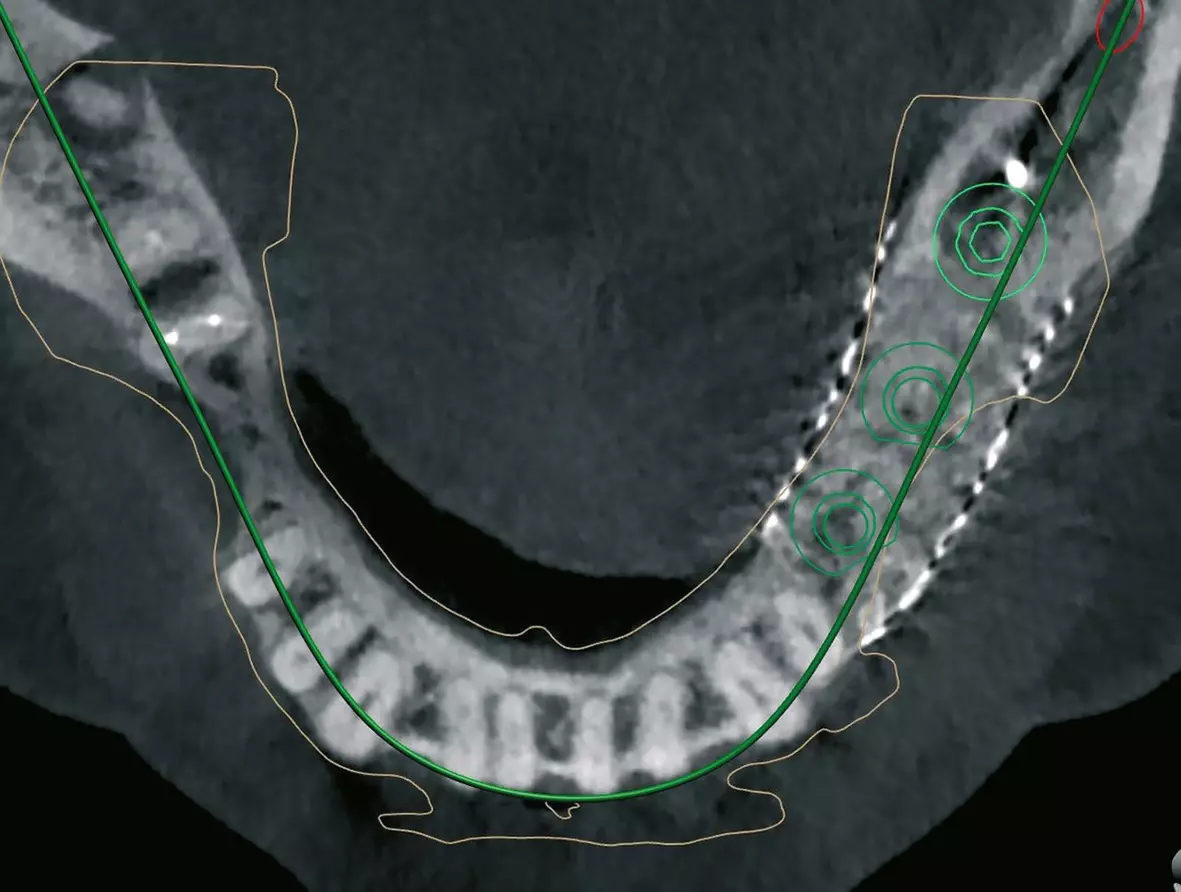

Nach 6 Monaten Einheilzeit wurde für eine exakte Planung präoperativ ein OPG und ein DVT angefertigt und die genauen Implantatpositionen mittels Software ermittelt (Abb. 4 a-c). Klinisch und radiologisch stellte sich ein ausreichendes Knochenangebot für eine Implantation dar (Abb. 3 und 4).

Der zweite Patientenfall beschäftigt sich mit einer Patientin Anfang 60, die sich mit einer verkürzten Zahnreihe bis zum Zahn 34 und dem Wunsch der Versorgung des III. Quadranten zu uns in die Praxis kam (Abb. 17a). Allgemeinanamnestisch besteht ein Diabetes mellitus, Sarkoidose und eine Primärprophylaxe mit ASS 100 mg. Die Zähne im III. Quadranten sind schon vor mehreren Jahren verloren gegangen, was die starke vertikale und horizontale Atrophie des Kieferkamms erklärt (Abb. 17b). Nach ausführlicher Aufklärung über alle Behandlungsmöglichkeiten und entstehende Kosten, entschied sich die Patientin für eine festsitzende Implantatversorgung mit drei Implantaten zum Ersatz der Zähne 45-47. Bei der Planung der Implantate zeigte sich das stark ausgeprägte horizontale und vertikale Knochendefizit, was den Knochenaufbau mit einem individuell geplanten Titangitter (Yxoss, ReOss) notwendig machte. Mittels DVT-Daten und entsprechender Planungssoftware wurde das 3D-Gitter individuell, entsprechend der anatomischen Verhältnisse und des benötigten Knochenvolumens, geplant und angefertigt (Abb. 17 c-e).